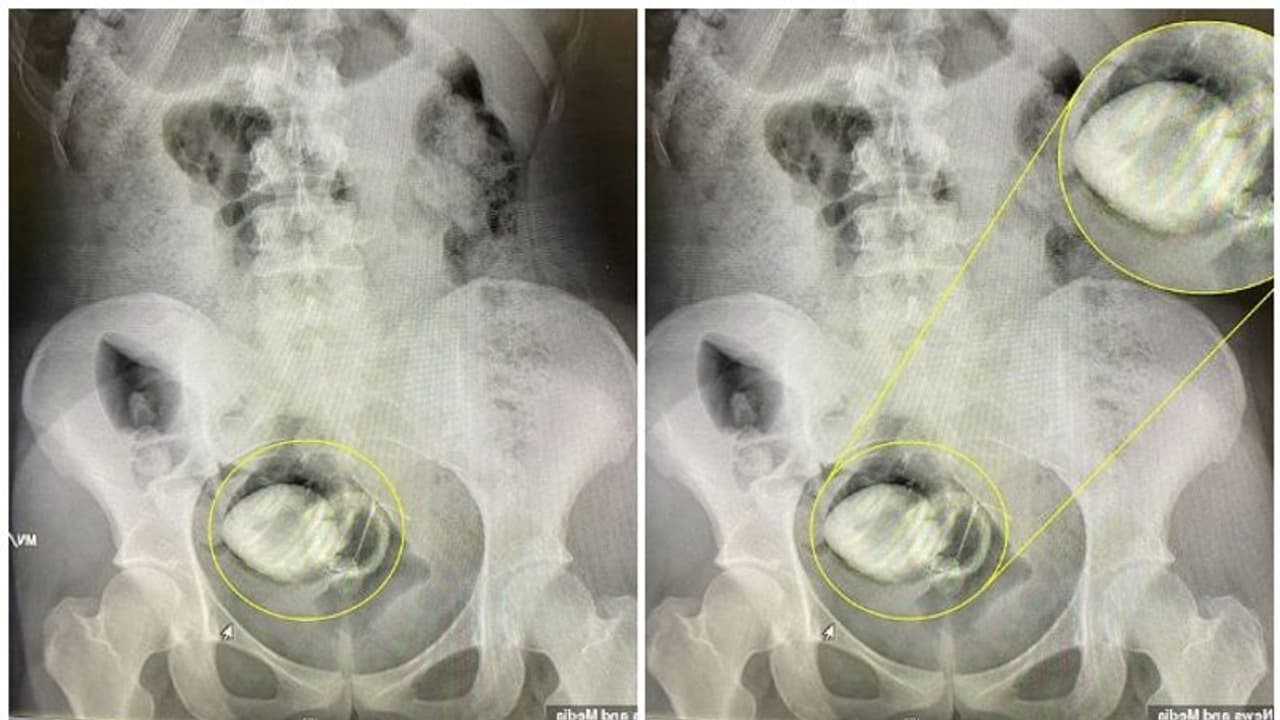

മലദ്വാരത്തിൽ സെക്സ് ടോയ് (Sex Toy) കുടുങ്ങിയ യുവതിയെ രക്ഷപെടുത്തി ഡോക്ടർമാർ. 10.3 സെന്റീമീറ്റർ നീളവും 4.4 സെന്റീമീറ്റർ വീതിയുമുള്ള സിലിക്കൺ ടോയ് ആണ് ഡോക്ടർമാർ പുറത്തെടുത്തത്. അപ്രതീക്ഷിതമായിട്ടാണ് തന്റെ മലദ്വാരത്തിനുള്ളിൽ സെക്സ് ടോയ് പൂർണ്ണമായും കയറിപ്പോയതെന്ന് 20 വയസുകാരിയായ യുവതി പറഞ്ഞു.

അവരാണ് ആശുപത്രിയിൽ പോകാൻ നിർദ്ദേശിച്ചതെന്നും ഡെയിലി മെയിൽ റിപ്പോർട്ട് ചെയ്തു. അങ്ങനെ തന്റെ റൂംമേറ്റുമായി ആശുപത്രിയിലേക്ക് പോകാൻ തീരുമാനിച്ചത്. തുടർന്ന് അവിടെ വച്ചെടുത്ത എക്സ്-റേയിൽ സെക്സ് ടോയ് കുടുങ്ങി കിടക്കുന്നതായി കണ്ടെത്തിയത്. ക്രിസ്റ്റൽ കൊണ്ട് അലങ്കരിച്ചതായിരുന്നു സെക്സ് ടോയ്. ഡോക്ടർമാർക്ക് കൈകൊണ്ട് തന്നെ സെക്സ് ടോയ് നീക്കം ചെയ്യാൻ കഴിഞ്ഞു.